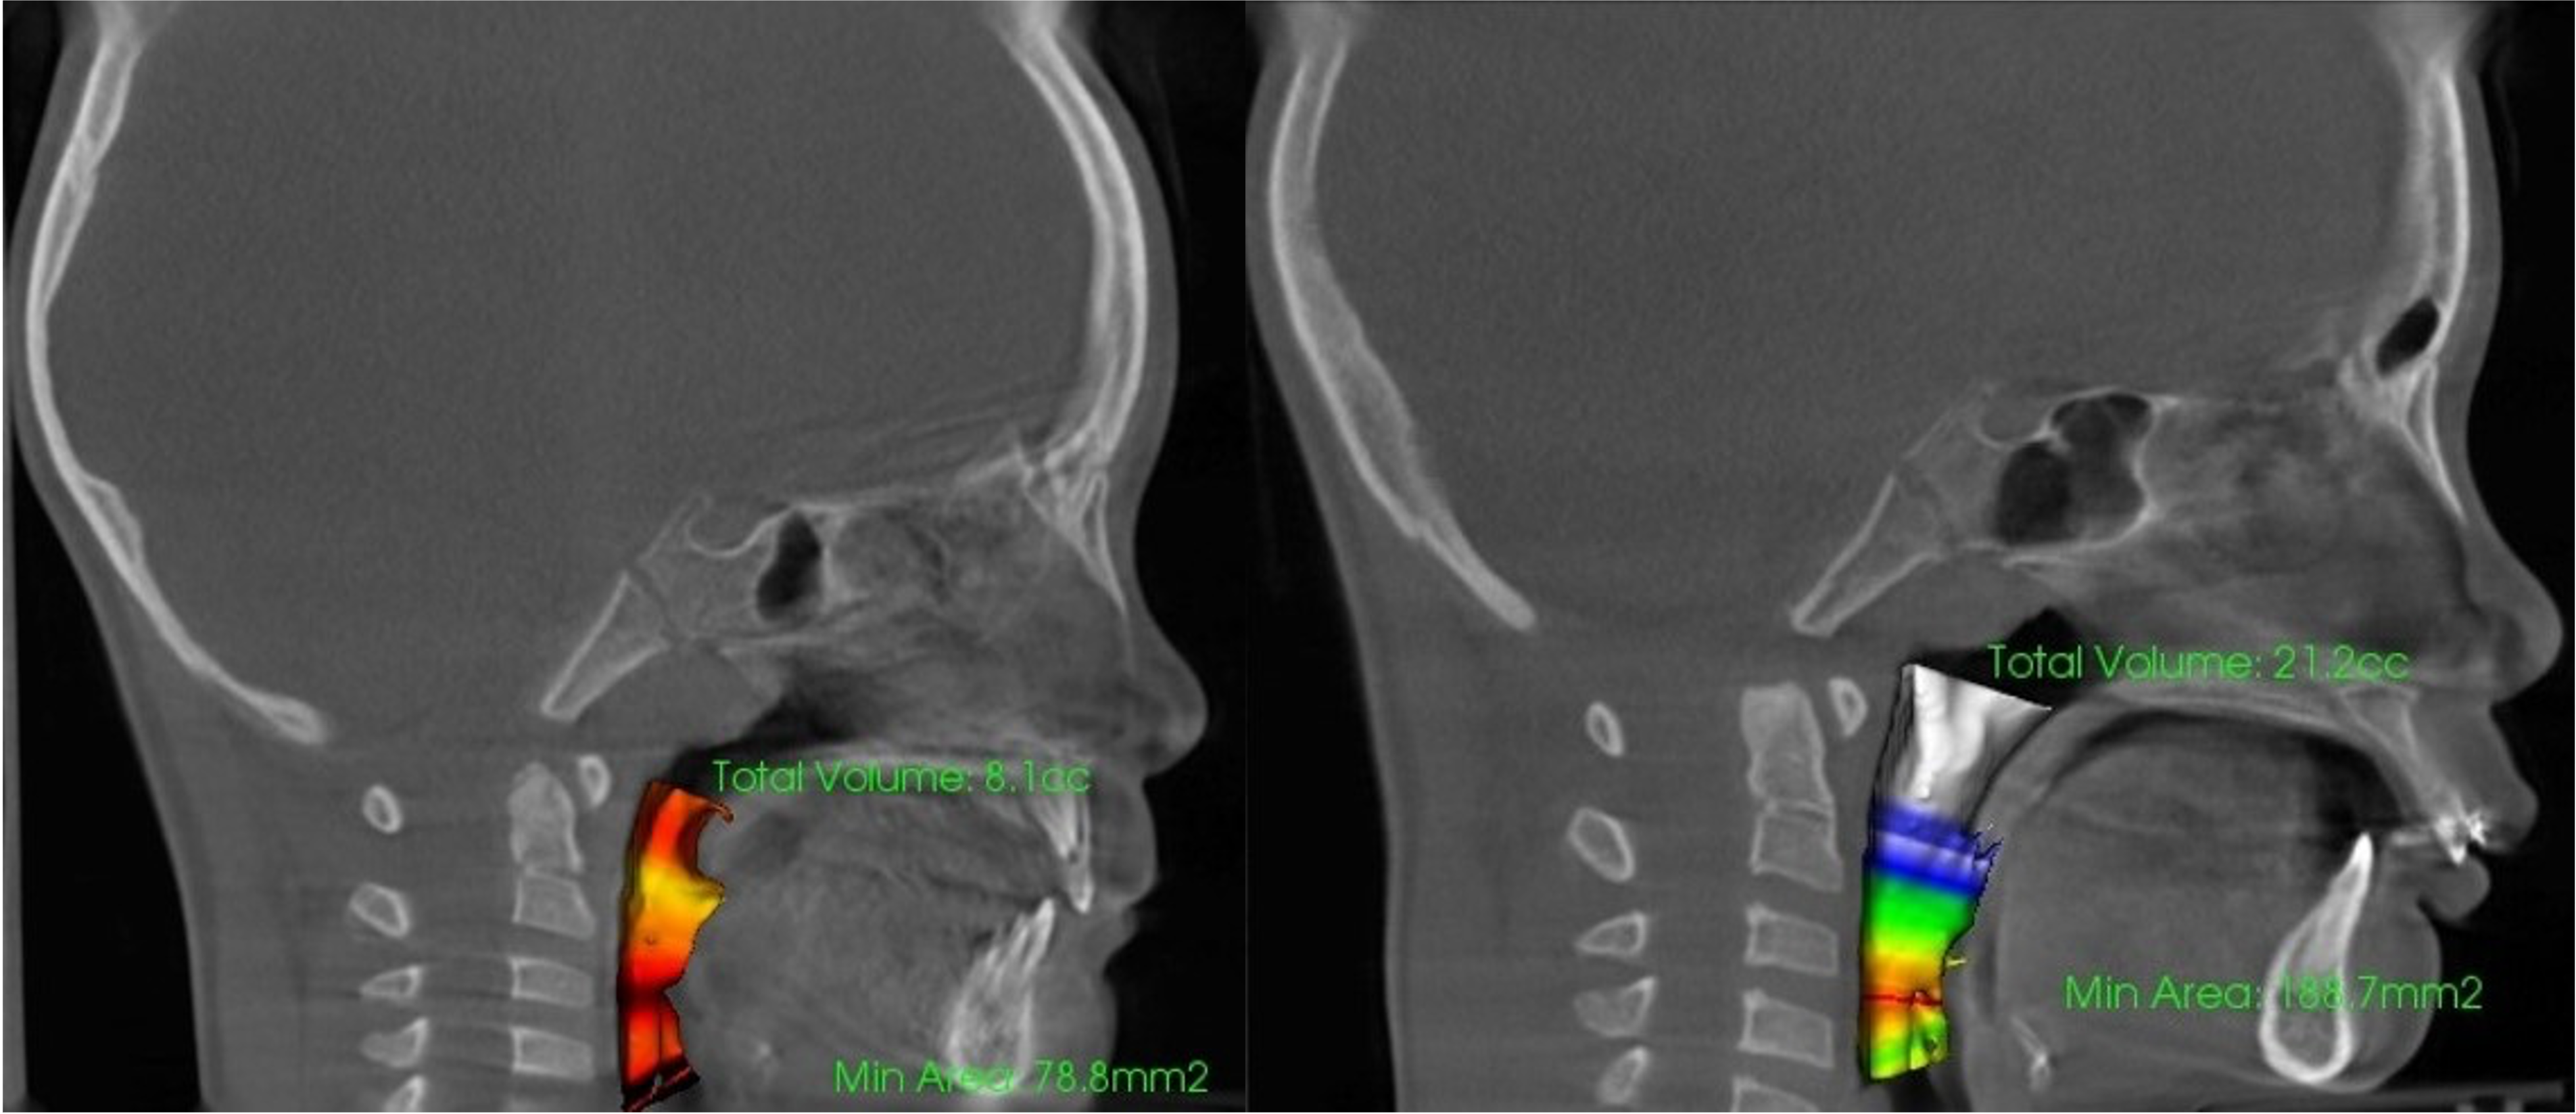

RAMPAによる気道容積の変化イメージ

三谷医師の開発から始まり、多くの経験を経て、現在ではその効果として歯並びはもちろんのこと、姿勢や鼻づまり、いびき、睡眠時無呼吸、喘息など、一見して歯並びとは関係のないことにも大きな改善が認められています。さらにお顔立ちにも変化が見られ、表情までもよくなっています。

審美よりむしろ、これら健康に関わることの方が、人生において、より大きな意義をもちます。実効的に骨格に関わり、結果が期待できるからこそ、RAMPAでは、このようなお伝えができます。

発達不良にあった骨格を、本来あるべき骨格へと整えることで、歯並びのみならず、気道や鼻腔の問題をはじめとする症状に対して改善が期待できます。現在は、バイオブロックから離れて、独自の進化を続けています。